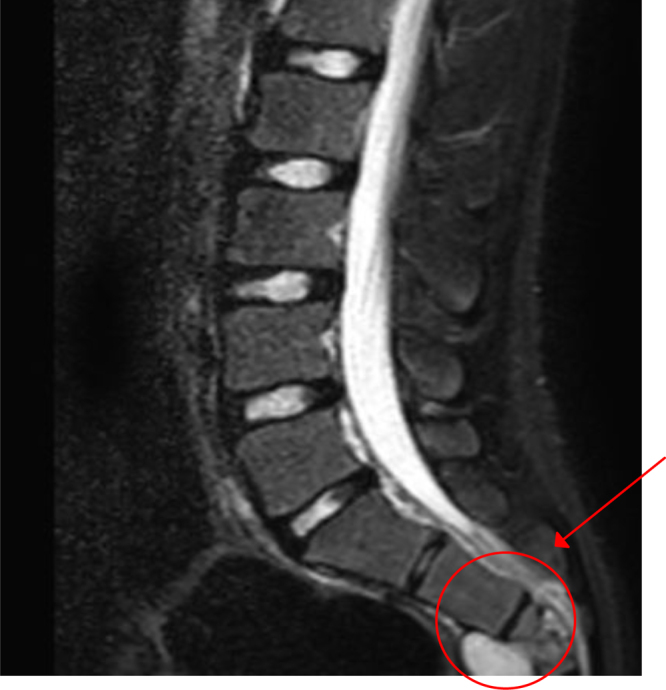

Observations: A 17-year-old male with a history of HC disease presented with low back pain radiating to both lower limbs, claudication, and chronic constipation for 5 years. Imaging revealed a large, multiloculated sacral cyst extending retrorectally and presacrally from S3 to S5, involving the spinal canal, compressing the rectum, and causing sacral erosion. A diagnosis of sacral hydatidosis was made, and the patient was started on albendazole, with surgical excision planned.